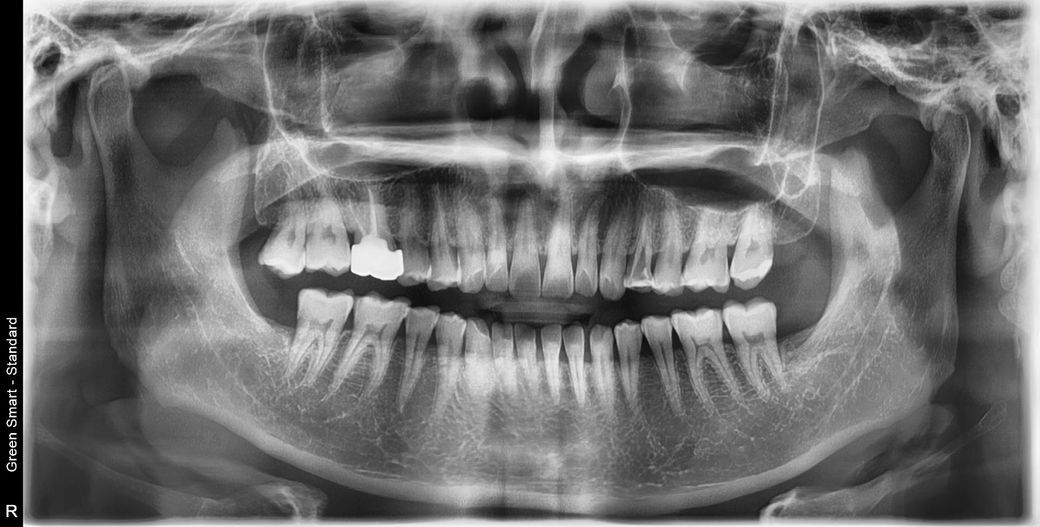

치과치료를 아무리 받아도 두통이 사라지질 않아요

신경치료만 7번은 받은거같은데 두통 머리통증 지근거림이

나아지질 않아요 세균이 뇌로 들어가고 있는거 같은 느낌입니다.

빨간색선으로 표시된부분이 금이나 충치같고 뿌리끝으로 충치나 금이 이어저서 뿌리쪽 뼈까지 녹고 염증 치근병소를 만든거 아닐까싶어요

사진보시구 한번 도움주세요 원인도 도통모르겠고

의사샘은 신경치료만 게속 하시는데 머리지근거림은 나아지질않고

치료는 포기하고 너무힘들어 발치할려고 합니다 발치전 마지막질문

드려봐요ㅠ 원인이라도 알고싶네요

사진상으로 보면 신경관이 많이 막혀 잇는 상태인거 같습니다 저 뿌리쪽에 신경이 제거가 되지 않는게 원인이라면 대학병원 보존과를 가보시거나 발치를 해야될것같습니다.

이미 해당 치아의 신경관 상단부는 확대가 많이 된 상태입니다. 하단부 분지부에서 놓친 신경관이 있을 수도 있고, 뿌리쪽 미세 크랙이 있을 수도 있습니다. 방사선 사진에서 표시한 게 크랙으로 보여지진 않습니다.